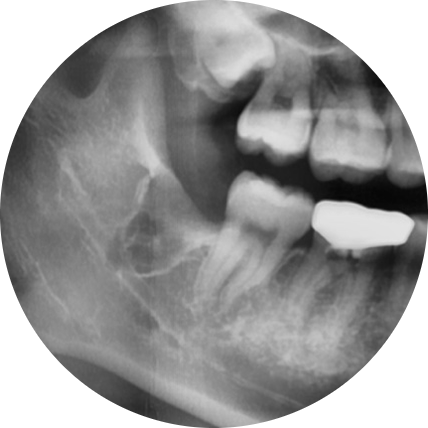

바른영치과 매복사랑니 발치사례

반대로 사랑니가 잘 자리를 잡고 났고, 구강청결 유지가 잘 이루어지기만 한다면 굳이 사랑니발치를 하실 필요는 없습니다. 그러나 아까 말씀드린 것처럼 사랑니가 일부 잇몸만 뚫고 나오는 비스듬시 자리하는 반매복 사랑니이거나 잇몸을 미처 뚫지 못해 잇몸 아래에서 자라고 있는 완전 매복 사랑니의 경우, 그리고 매복여부 상관없이 발치하는 것이 유리합니다.

단, 사랑니발치는 정상적으로 나지 않고 조금이라도 잇몸에 매복이 되어 있는 경우에는 잇몸절개 후 발치를 진행해야 하는데요. 하지만 잇몸에는 수많은 신경과 안면 감각기관이 모여 있어 난도 높은 치과진료 과목으로 손꼽힙니다. 때문에 옥수역치과 선택 시에는 사랑니발치 사례 경험이 많은 의료진이 있는지를 살펴보고 선택할 필요가 있습니다.

옥수역치과에서는 3D-CT를 통해 환자의 구강상태를 면밀히 살펴 사랑니의 매복 여부 및 형태 등을 확인한 후 적합한 치료방법을 통해 난도 높은 사랑니 발치를 도와드리고 있습니다. 또한 사랑니발치 시 부담을 느끼게 될 통증에 대한 두려움을 줄여드리기 위해 디지털 무통마취기 또한 구비해 두고 있습니다.